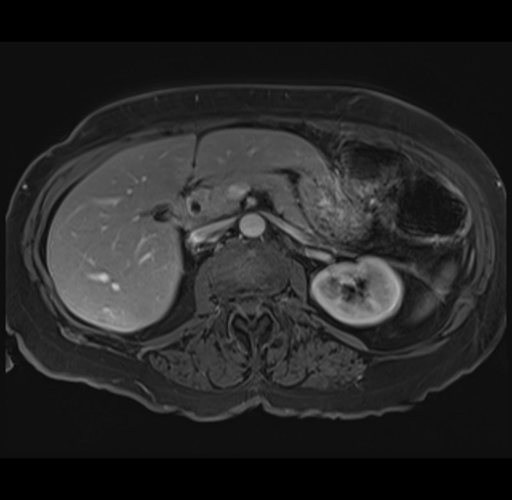

MRI T1